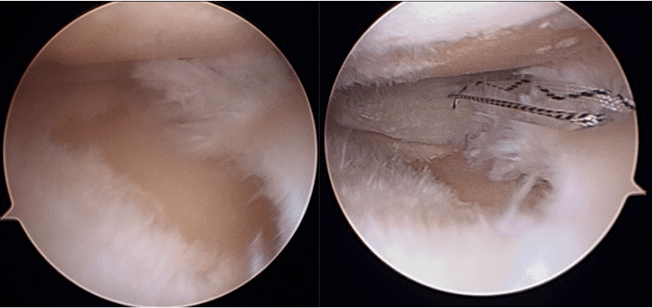

前十字靱帯損傷は、スポーツ活動においてパフォーマンスを著しく低下させるだけでなく、2次性変形性膝関節症を引き起こします。その頻度は、12年で63%、30年で86%とも言われております。膝前十字靭帯機能を再獲得するため、我々は、解剖学的な靭帯付着に正確に長方形骨孔を作成した骨付膝蓋腱を用いた方法で再建しております。前十字靱帯損傷には半月板損傷や軟骨損傷を合併することが多く、半月板損傷には半月板縫合術を、軟骨損傷には骨穿孔術や骨軟骨移植術、自家培養軟骨移植術を併用しております。

半月板は、線維軟骨でできており、膝関節においてはクッションの役割があります。半月板の損傷が起こると続いて軟骨損傷が生じ、時間が経つと関節の変形が生じてきます。

我々は、軟骨機能を温存するため、inside-out法による強固な縫合を、関節鏡を用いて行っております。より強固に縫合するため特殊な縫合方法で行っております。下肢アライメント不良がある膝に対しては、アライメント矯正手術を併用した半月板縫合術も行う場合もあります。